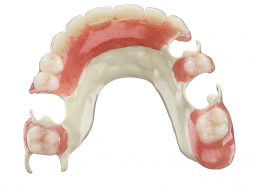

Ultaire™ AKP is an innovative aryl ketone polymer (AKP) formulated to meet critical performance requirements for removable partial dentures (RPDs). This high-performance polymer fits into your digital workflow and goes from CAD to finish in one day. Ultaire™ AKP was developed by Solvay Dental 360™, part of Solvay, a world leader in metal-replacing materials for the healthcare industry.

RPDs made from Ultaire® AKP are:

· Metal-free, comfortable, biocompatible

· Lightweight; 60% lighter than metal

· Bone-like and tooth supported

· Esthetically pleasing